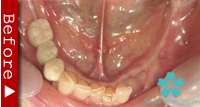

数本の歯を失った場合

この場合もインプラントが理想的な解決法となります。数本のインプラントを歯のない部分に入れ、これを土台としてヘッド部にブリッジをかぶせます。